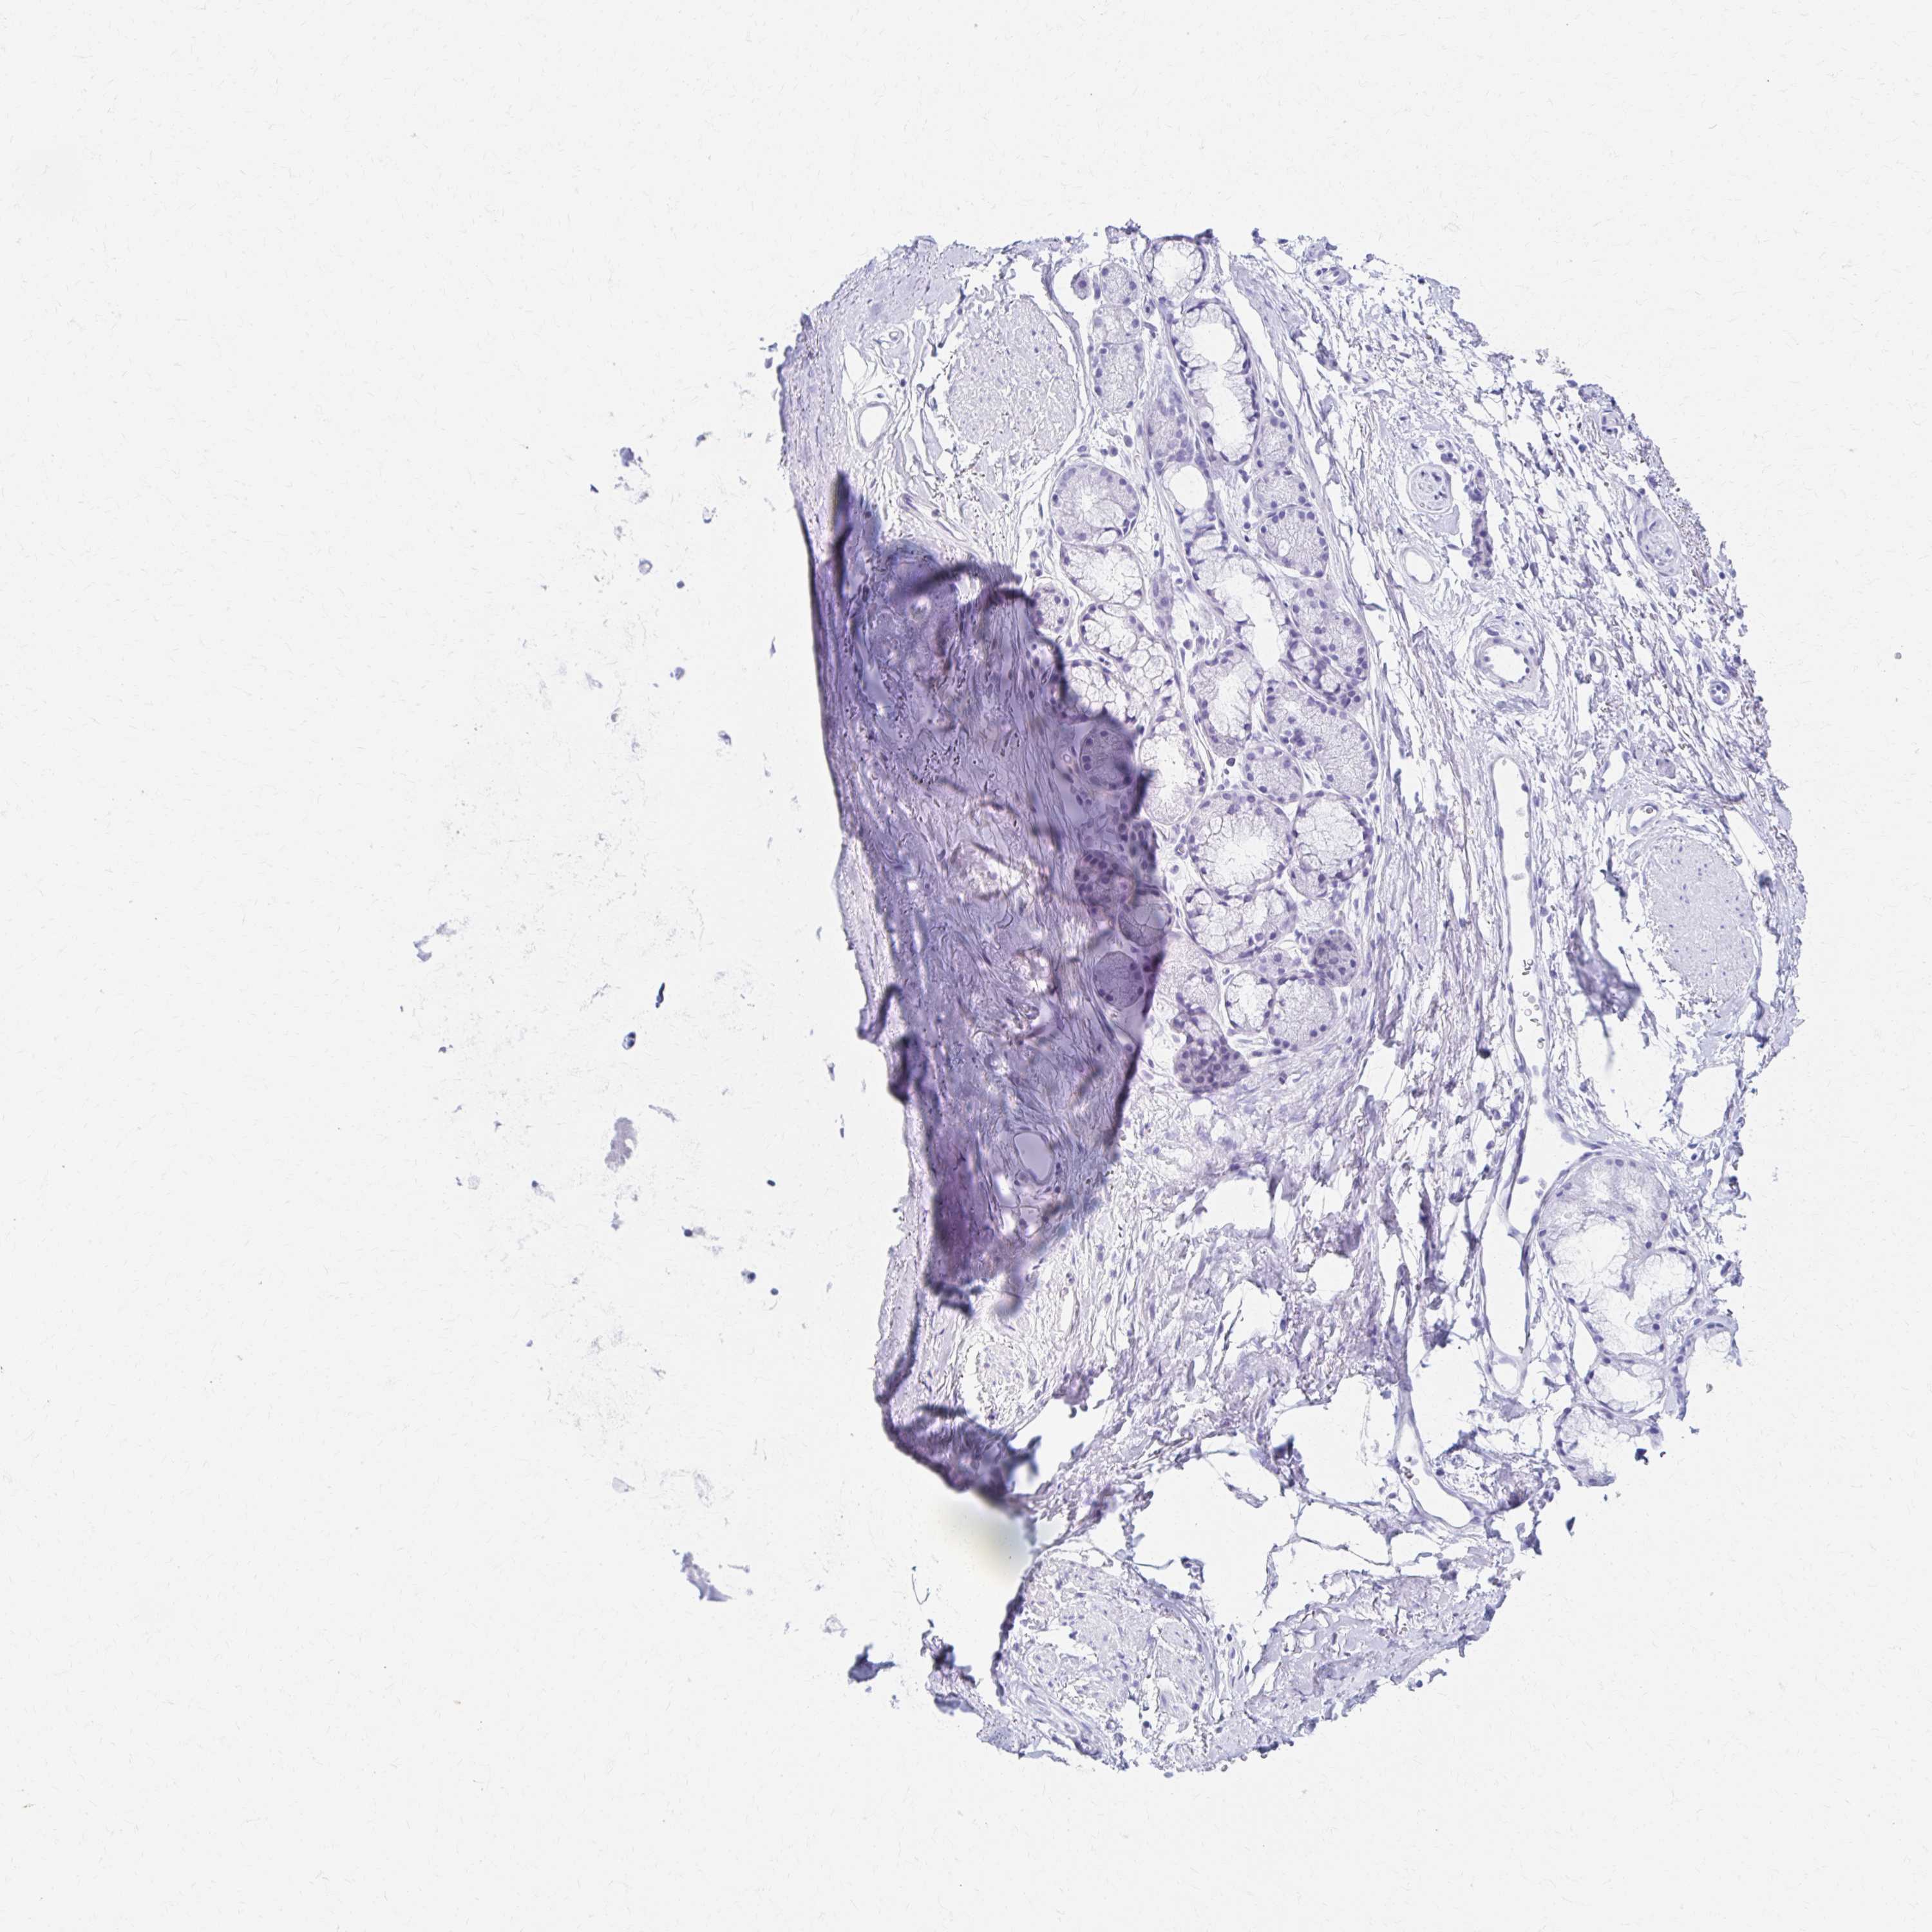

PRKCG